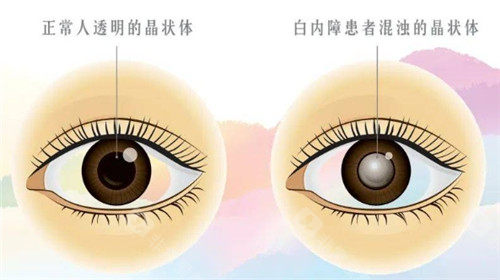

白内障是一种常见的眼科疾病,尤其在老年人群体中发病率较高。

医院采用的手术方式主要有超声乳化白内障吸除术联合人工晶状体植入术等,这些手术方式具有切口小、改善快等优点。